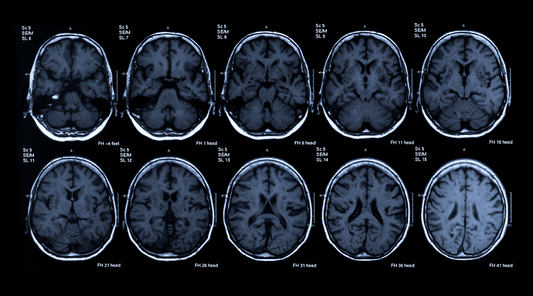

Read MoreIs your brain healthy? Here's a guide to suppor...

Learn the difference between occasional forgetfulness and mild cognitive impairment, how to assess your own brain health, and ways to support your brain.